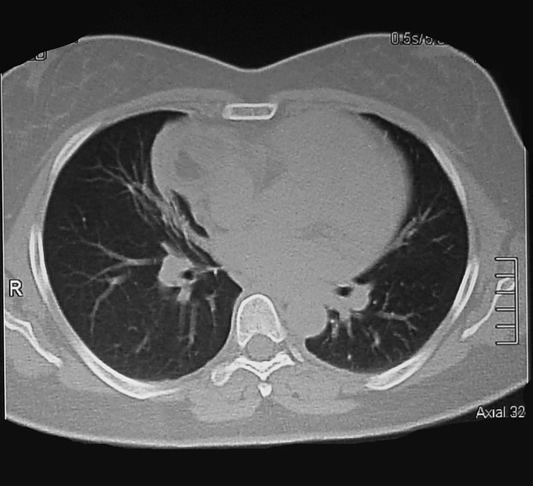

tomografia Corte Axial 31 ventana pulmonar

tomografia Corte Axial 32 ventana pulmonar

Corte Axial en hileo pulmonar

La lesión con forma de pera, encapsulada y densidad heterogénea, su parte mas amplia para cardiaca derecha ocupa el ángulo pleuropericardico anterior y el cuello posterior de la lesión en relación con el seno de la arteria pulmonar y la vena cava superior.

El seno cardiofrenico esta libre y sin derrame pleural.

Corte Axial debajo de los hileos

Un corte axial mas bajo al precedente: la lesión en su mayor diámetro, en relación adosada con la aurícula derecha y el cono aórtico, parece comprimir el parenquima pulmonar ocasionando atelectasia laminar.